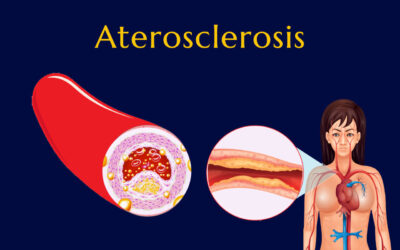

Parece que las estructuras celulares que componen el “endotelio” (la capa de tejido que se ubica en el interior de las arterias) sufren “escoriaciones microscópicas” que favorecen la acumulación de grasa y plaquetas con la subsecuente “aterosclerosis”.

Además, esta lesión endotelial causa inflamación local que, a la larga contribuye a empeorar la formación de “placa de ateroma”.

A consecuencia de la enfermedad de estas arterias pequeñas “arteriopatía coronaria aterosclerótica” ocurre disminución y hasta obstrucción del flujo sanguíneo hacia las fibras del músculo cardíaco causando muerte celular: Infarto.